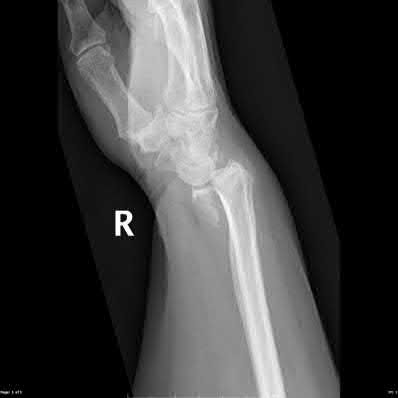

Question 6:

A 22-year-old male falls onto an outstretched hand and sustains a displaced fracture through the proximal pole of the scaphoid. Avascular necrosis of the proximal pole is highly likely due to the disruption of its primary vascular supply. Which vessel provides this critical retrograde perfusion?

Options:

Correct Answer: Dorsal carpal branch of the radial artery

Explanation:

The primary blood supply to the scaphoid is from the dorsal carpal branch of the radial artery, which enters the dorsal ridge of the scaphoid at the waist and courses proximally. This retrograde blood flow makes proximal pole fractures highly susceptible to avascular necrosis and nonunion. The superficial palmar branch provides a minor supply (about 20%) to the distal pole.